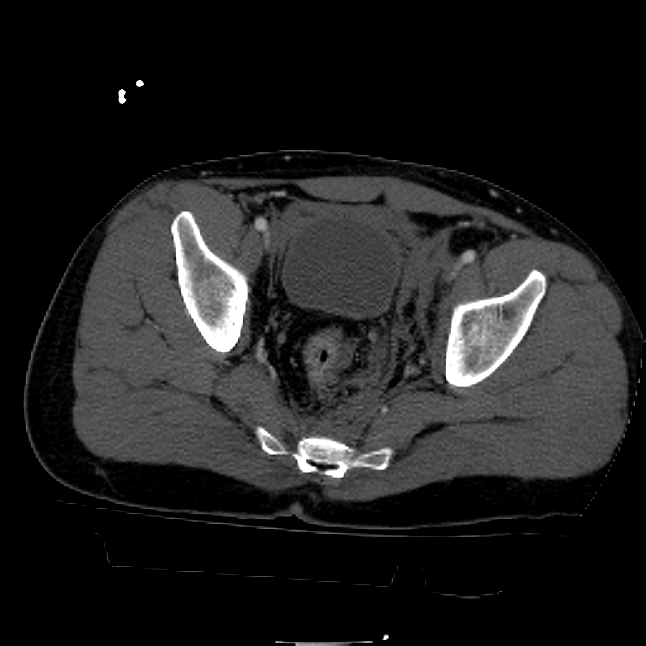

25 yo brittle diabetic, became hypoglycemic and passed out on his motorcycle. Sustained bilateral lateral Hoffa fractures with associated LCL injury on the right and right distal radius fracture. I have questions regarding his pelvic ring/acetabular fracture on the left. Appears to be a very low posterior column fracture with associated posterior wall, marginal impaction. Superior and inferior rami fractures as well on the left giving him a floating segment of inf ramus/ischium/posterior column, but no detectable posterior ring injury. Should the posterior column/posterior wall fracture be addressed surgically because of the marginal impaction? Or is this fracture low enough to be treated non-operatively? I appreciate the input.

It's an interesting case. The plain films show the impaction, but most of the joint looks pretty good. The CT cuts look awful, though.

The impaction is so big I don't think I would ignore it. It IS down low, but it takes up almost the whole southern hemisphere of his joint.

interesting case. I believe a common mistake is saying that the dome is ok so I can treat this nonoperatively. This only works for tr and t type fractures not posterior column posterior wall fractures. Matta's results show no difference with impaction. Mine show worse results with impaction but still better results than nonoperatively. The really bad ones are the elderly with dome impaction but I ve been surprised by a few of those as well. This I more posterior and I think will do well with good fixation. This means a good reefing behind the piece (?2.7mm or 2.0mm to get more screws) to prevent the late collapse. I also am very gingerly with their post op tdwb x 3 months with no pt to that extremity. Hope this helps.